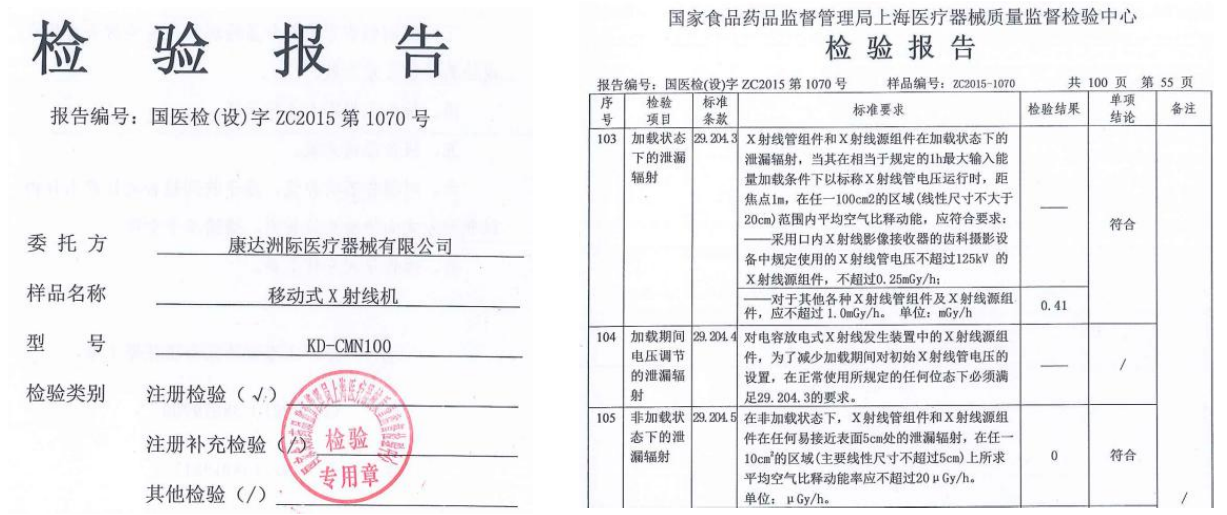

优化安全的低剂量辐射管控

微米级焦点球管设计及低剂量曝光控制,使得产品整机的漏辐射保持在较低的水平。 据国家漏辐射检测标准可知,在加载状态下的漏辐射应不超过 1.0mGy/h,而非加载状态下的漏辐射应不超过 20μGy/h。 CMN100 关于该项的检测结果为加载状态下不高于 0.41mGy/h,非加载状态下为 0μGy/h。